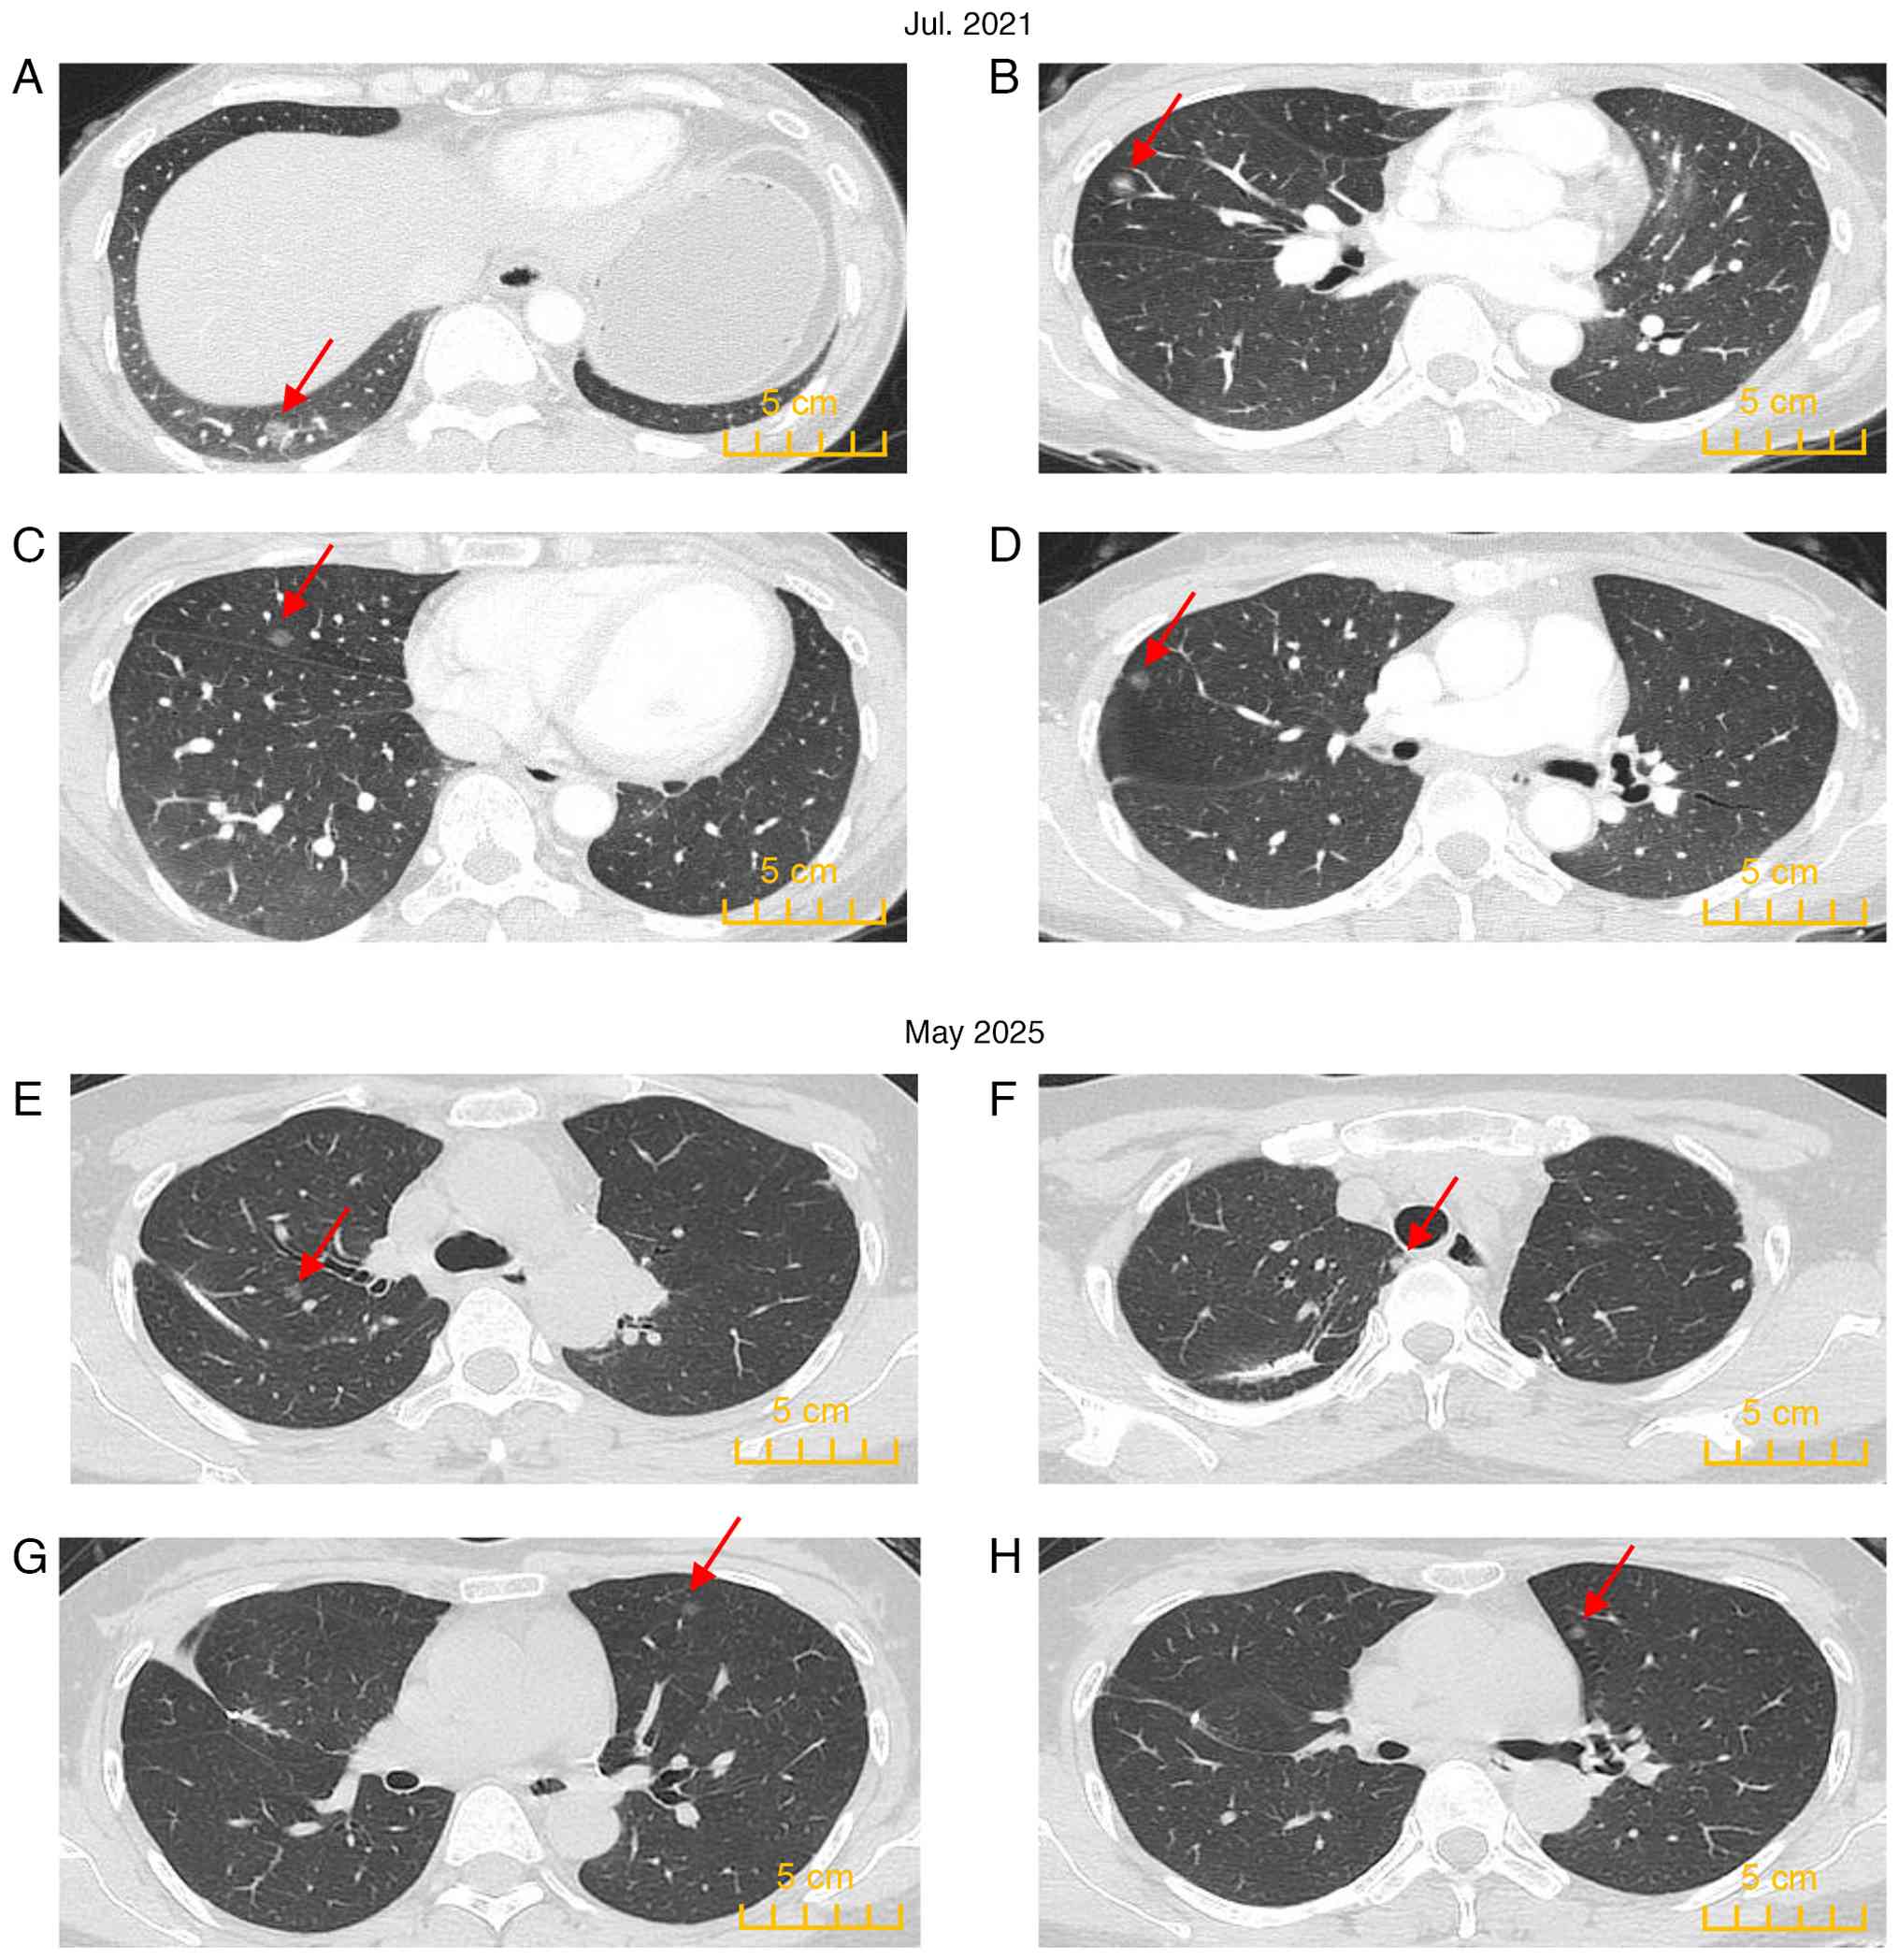

Patient CT images. (A) The main

lesion in the lungs (left upper lobe lesion 1); a solid mass shadow

in the irregular part of the anterior segment of the left upper

lobe with blurred edges, visible lobulation, spiculation and

cavitation signs, local pleural traction signs, irregular bronchial

stenosis and occlusion in the lesion. (B-D) The main remaining

lesions (GGNs) of the left upper lung. (E and F) Main lesions

(GGNs) of the right middle lung. (G) Main lesions (GGNs) of the

right upper lung. (H) Main lesions (GGNs) of the right lower lung.

GGNs, ground-glass nodules.

Figure 2

Patient CT images. (A) The main lesion in the lungs (left upper lobe lesion 1); a solid mass shadow in the irregular part of the anterior segment of the left upper lobe with blurred edges, visible lobulation, spiculation and cavitation signs, local pleural traction signs, irregular bronchial stenosis and occlusion in the lesion. (B-D) The main remaining lesions (GGNs) of the left upper lung. (E and F) Main lesions (GGNs) of the right middle lung. (G) Main lesions (GGNs) of the right upper lung. (H) Main lesions (GGNs) of the right lower lung. GGNs, ground-glass nodules.

Following chemotherapy, the patient still exhibited multiple high-risk nodules in the lungs in July 2021 (Fig. 6A-D) and the desired pulmonary nodule regression was not achieved. At this time, the pulmonary function retest values were as follows: FEV1, 1.41 l; FEV1%, 54.15%; FVC, 2.05 l; FVC%, 67.08%; and FEV1/FVC, 68.97%. The patient exhibited no asthma in their daily life. High-risk residual lesions were recommended for treatment and both surgery and thermal ablation were considered options. However, the patient elected to undergo surgery. As a result, the patient underwent a second surgery in August 2021. Considering that excessive resection of lung tissue may lead to insufficient pulmonary functional reserve, wedge resection was performed on each lobe of the right lung.

CT images after the two surgeries.

(A-D) CT images after the first surgery in July 2021. High-risk

residual lung nodules remained in the right lower and middle lungs.

(E-H) CT images after the second surgery in May 2025. The residual

lung nodules were stable small GGN stable and have not

progressed.

Figure 6

CT images after the two surgeries. (A-D) CT images after the first surgery in July 2021. High-risk residual lung nodules remained in the right lower and middle lungs. (E-H) CT images after the second surgery in May 2025. The residual lung nodules were stable small GGN stable and have not progressed.